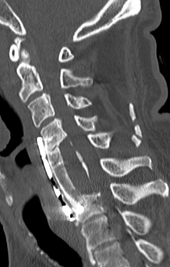

思春期特発性側弯症の全脊椎レントゲンで背骨が大きくSの字に曲がっています。最も曲がっている箇所は80°で、高度側弯に分類されます。後方からの脊柱側弯矯正術で真っ直ぐになっています。

また、側弯の患者さんは一般的にフラットバックと言って背骨の生理的後弯(背中の丸み)が失われています。この症例も胸椎後弯角は5°で典型的なフラットバックを呈しています(正常は20°~30°程度です)。この影響は頸椎の形態にも影響を及ぼし、この症例も頸椎が既に後弯(正常は前弯)しています。(黄色矢印)

ストレートネックという頸椎の前弯が消失して頸部の愁訴が出現する病態は広く知られていますが、更に変形が進行した頸椎と考えて下さい。

以前はこのフラットバック(生理的胸椎後弯の消失)を治すことは困難でしたが、当院では手術方法の様々な工夫により生理的胸椎後弯の復元を行っております。この症例は術後に胸椎後弯角が26°と改善しており、生理的な胸椎後弯が形成されています。さらに頸椎後弯にも良い影響を及ぼし、術後は頸椎前弯化が得られつつあるのが分かります。(黄色矢印)